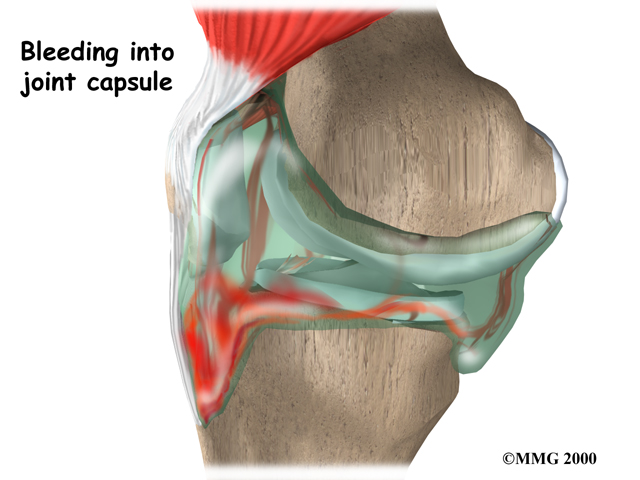

The symptoms following a tear of the ACL can vary. Some patients report hearing and/or feeling a pop. Usually, the knee joint swells within a short time following the injury. This is due to bleeding into the knee joint from torn blood vessels in the damaged ligament. The instability caused by the torn ligament leads to a feeling of insecurity and giving way of the knee, especially when trying to change direction on the knee. The knee may feel like it wants to slip backwards. There may be activity-related pain and/or swelling. Walking downhill or on ice is especially difficult. And you may have trouble coming to a quick stop.

In the acute (sudden) injury, the swelling is a good indicator. A good rule of thumb that orthopedic surgeons use is that any tense swelling that occurs within two hours of a knee injury usually represents blood in the joint, or a hemarthrosis. If the swelling occurs the next day, the fluid is probably from the inflammatory response.

If there is fluid associated with your ACL injury, your doctor may need to place a needle in the swollen joint and aspirate (drain as much fluid as possible) the give relief from the swelling. The procedure also provides useful information to your doctor. If blood is found when draining the knee, there is about a 70 percent chance it represents a torn ACL. This fluid can also show if the cartilage on the surface of the knee joint was injured.